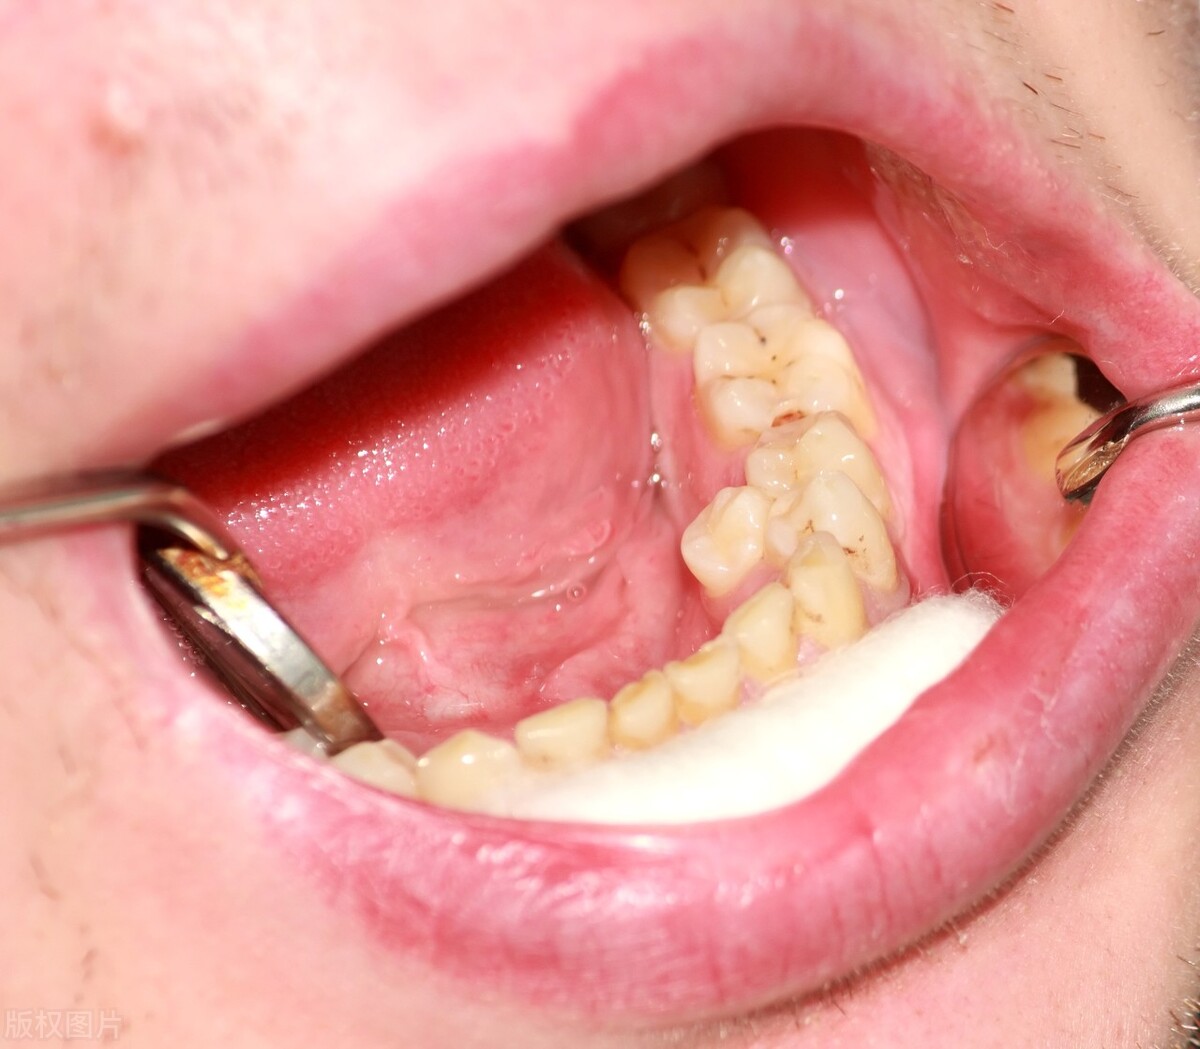

3、多生牙

我们正常的成年人共有28颗牙齿,以及1~4颗的智齿,多生牙就是指不在这些牙齿范围,异常生长出来的牙。因为多生牙会挤压我们正常牙齿的生长位置,造成牙齿拥挤、长不齐,甚至会造成孩子换牙的时候恒牙长不出来,引起 颌骨的囊肿 ,因此也是建议要拔除的。

多生牙